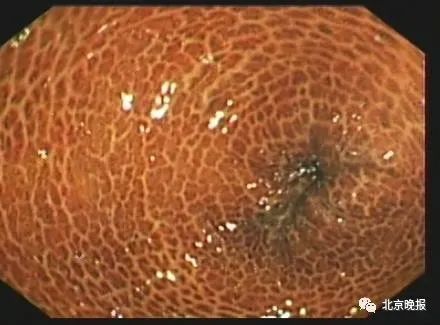

据钱江晚报报道,杭州63岁的王阿姨便秘多年,三年前开始吃酵素以后通畅了很多。近日,在一次结肠镜检查时,医生发现王阿姨的肠子布满了棕黑色的花纹,像“蛇皮”一样,患上了结肠黑变病。

今年7月,上海市同仁医院也介绍过一例相似病例,30岁的白领小刘常久坐缺少运动,受便秘困扰多年。做无痛结肠镜检查的结果显示:全结直肠黏膜豹纹样褐色素沉着,诊断为“结肠黑变病”。

结肠黑变病黏膜